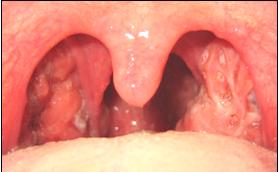

Las amígdalas ó anginas son un par de masas con aspecto de almendra formadas también por tejido linfoide. Cada una está situada a cada lado de la garganta. Muestran unas pequeñas depresiones llamadas criptas. Pueden verse relativamente fácil al abrir la boca, iluminando la garganta con una lamparita. Se cree que intervienen en la defensa contra las enfermedades; sin embargo, su infección crónica por virus y bacterias pueden provocar distintos tipos de afecciones.